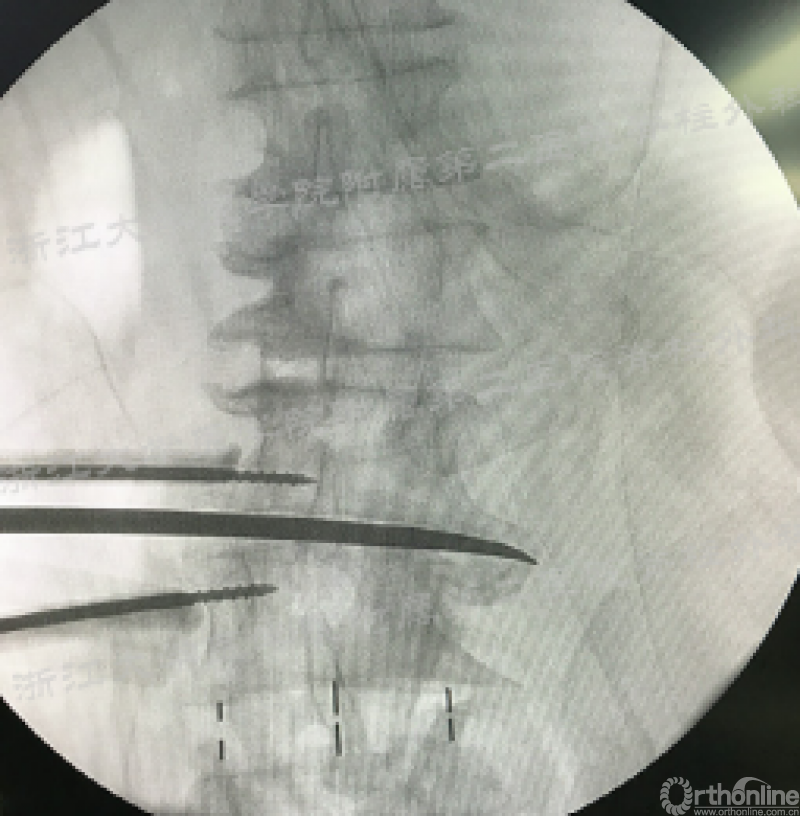

安全工作区域。A.根据术前椎间隙MRI横截面确定经腰大肌的安全工作区域;B.克氏针经安全工作区域置入椎间盘,再次定位椎间隙及确认安全工作区域;C.直视下避开生殖股神经(●),沿肌纤维方向劈开腰大肌(蓝色箭头所示);D.安装改良牵开器建立工作通道;E.X线透视进行显示椎间隙的处理及融合操作